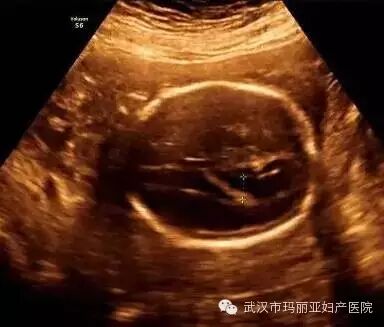

武汉玛丽亚妇产医院引进的世界领先的美国GE-E8四维彩超设备室目前世界上最先进、分辨率最高的彩色超声设备,具有即时立体成像、清晰准确的特点。

它能够多方位、多角度地观察宫内胎儿的生长发育情况,为早期诊断胎儿先天性体表畸形和发育异常提供科学依据。还能对胎儿的体表进行检查,如唇裂、脊柱裂、大脑、肾、 骨骼发育不良等,以便尽早的进行治疗。

玛丽亚美国GE-E8四维彩超排畸成功案例

案例二:胎儿侧脑室增宽